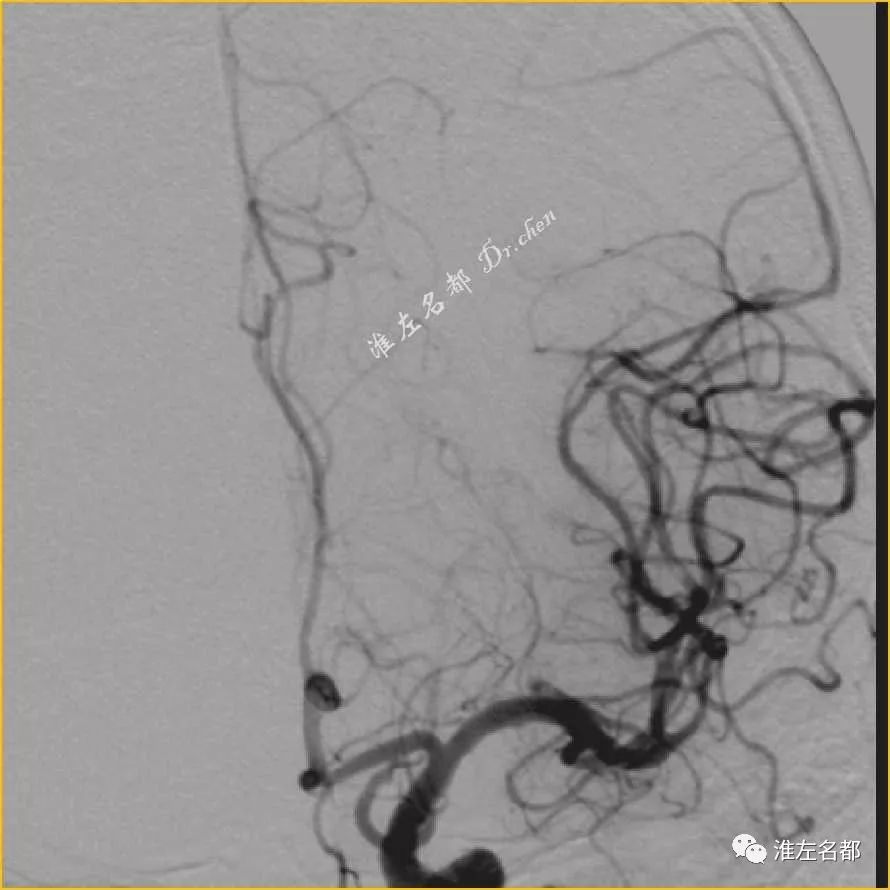

△DSA:左侧MCA主干闭塞

△DSA:取栓治疗后,左侧MCA闭塞再通